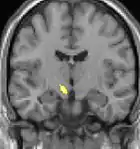

Positron emission tomography (PET) shows brain areas being activated during pain.

Voxel-based morphometry (VBM) shows brain area structural differences.

Positron emission tomography (PET) scans indicate the brain areas which are activated during attack only, compared to pain free periods. These pictures show brain areas that are active during pain in yellow/orange color (called "pain matrix"). The area in the center (in all three views) is specifically activated during CH only. The bottom row voxel-based morphometry (VBM) shows structural brain differences between individuals with and without CH; only a portion of the hypothalamus is different.[36]